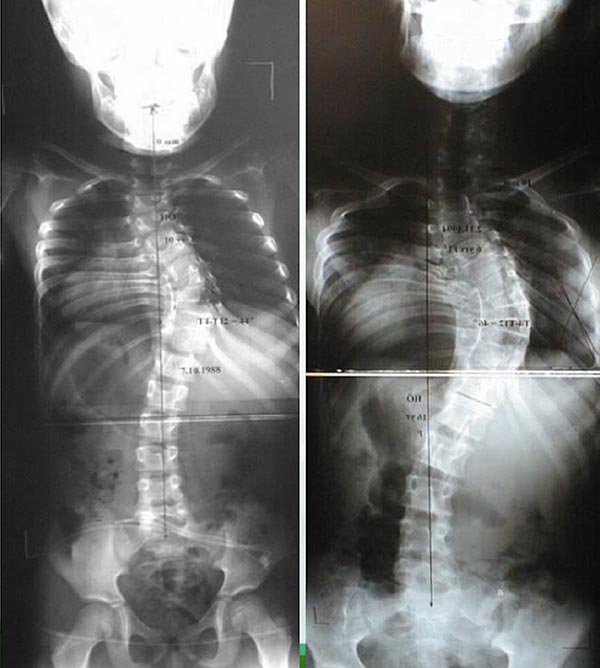

Radiografias são o principal método para o diagnóstico de escoliose congênita e suas mudanças evolutivas durante o seguimento1,6 (exemplo nas figuras 3 e 4). Sempre que possível, as radiografias devem ser feitas com o paciente de pé ou sentado devido a atuação da gravidade na possível acentuação da curva. A severidade das curvas é medida pelo ângulo de Cobb.

Figuras 3 e 4. Exemplos radiográficos demonstrando achados de escoliose congênita